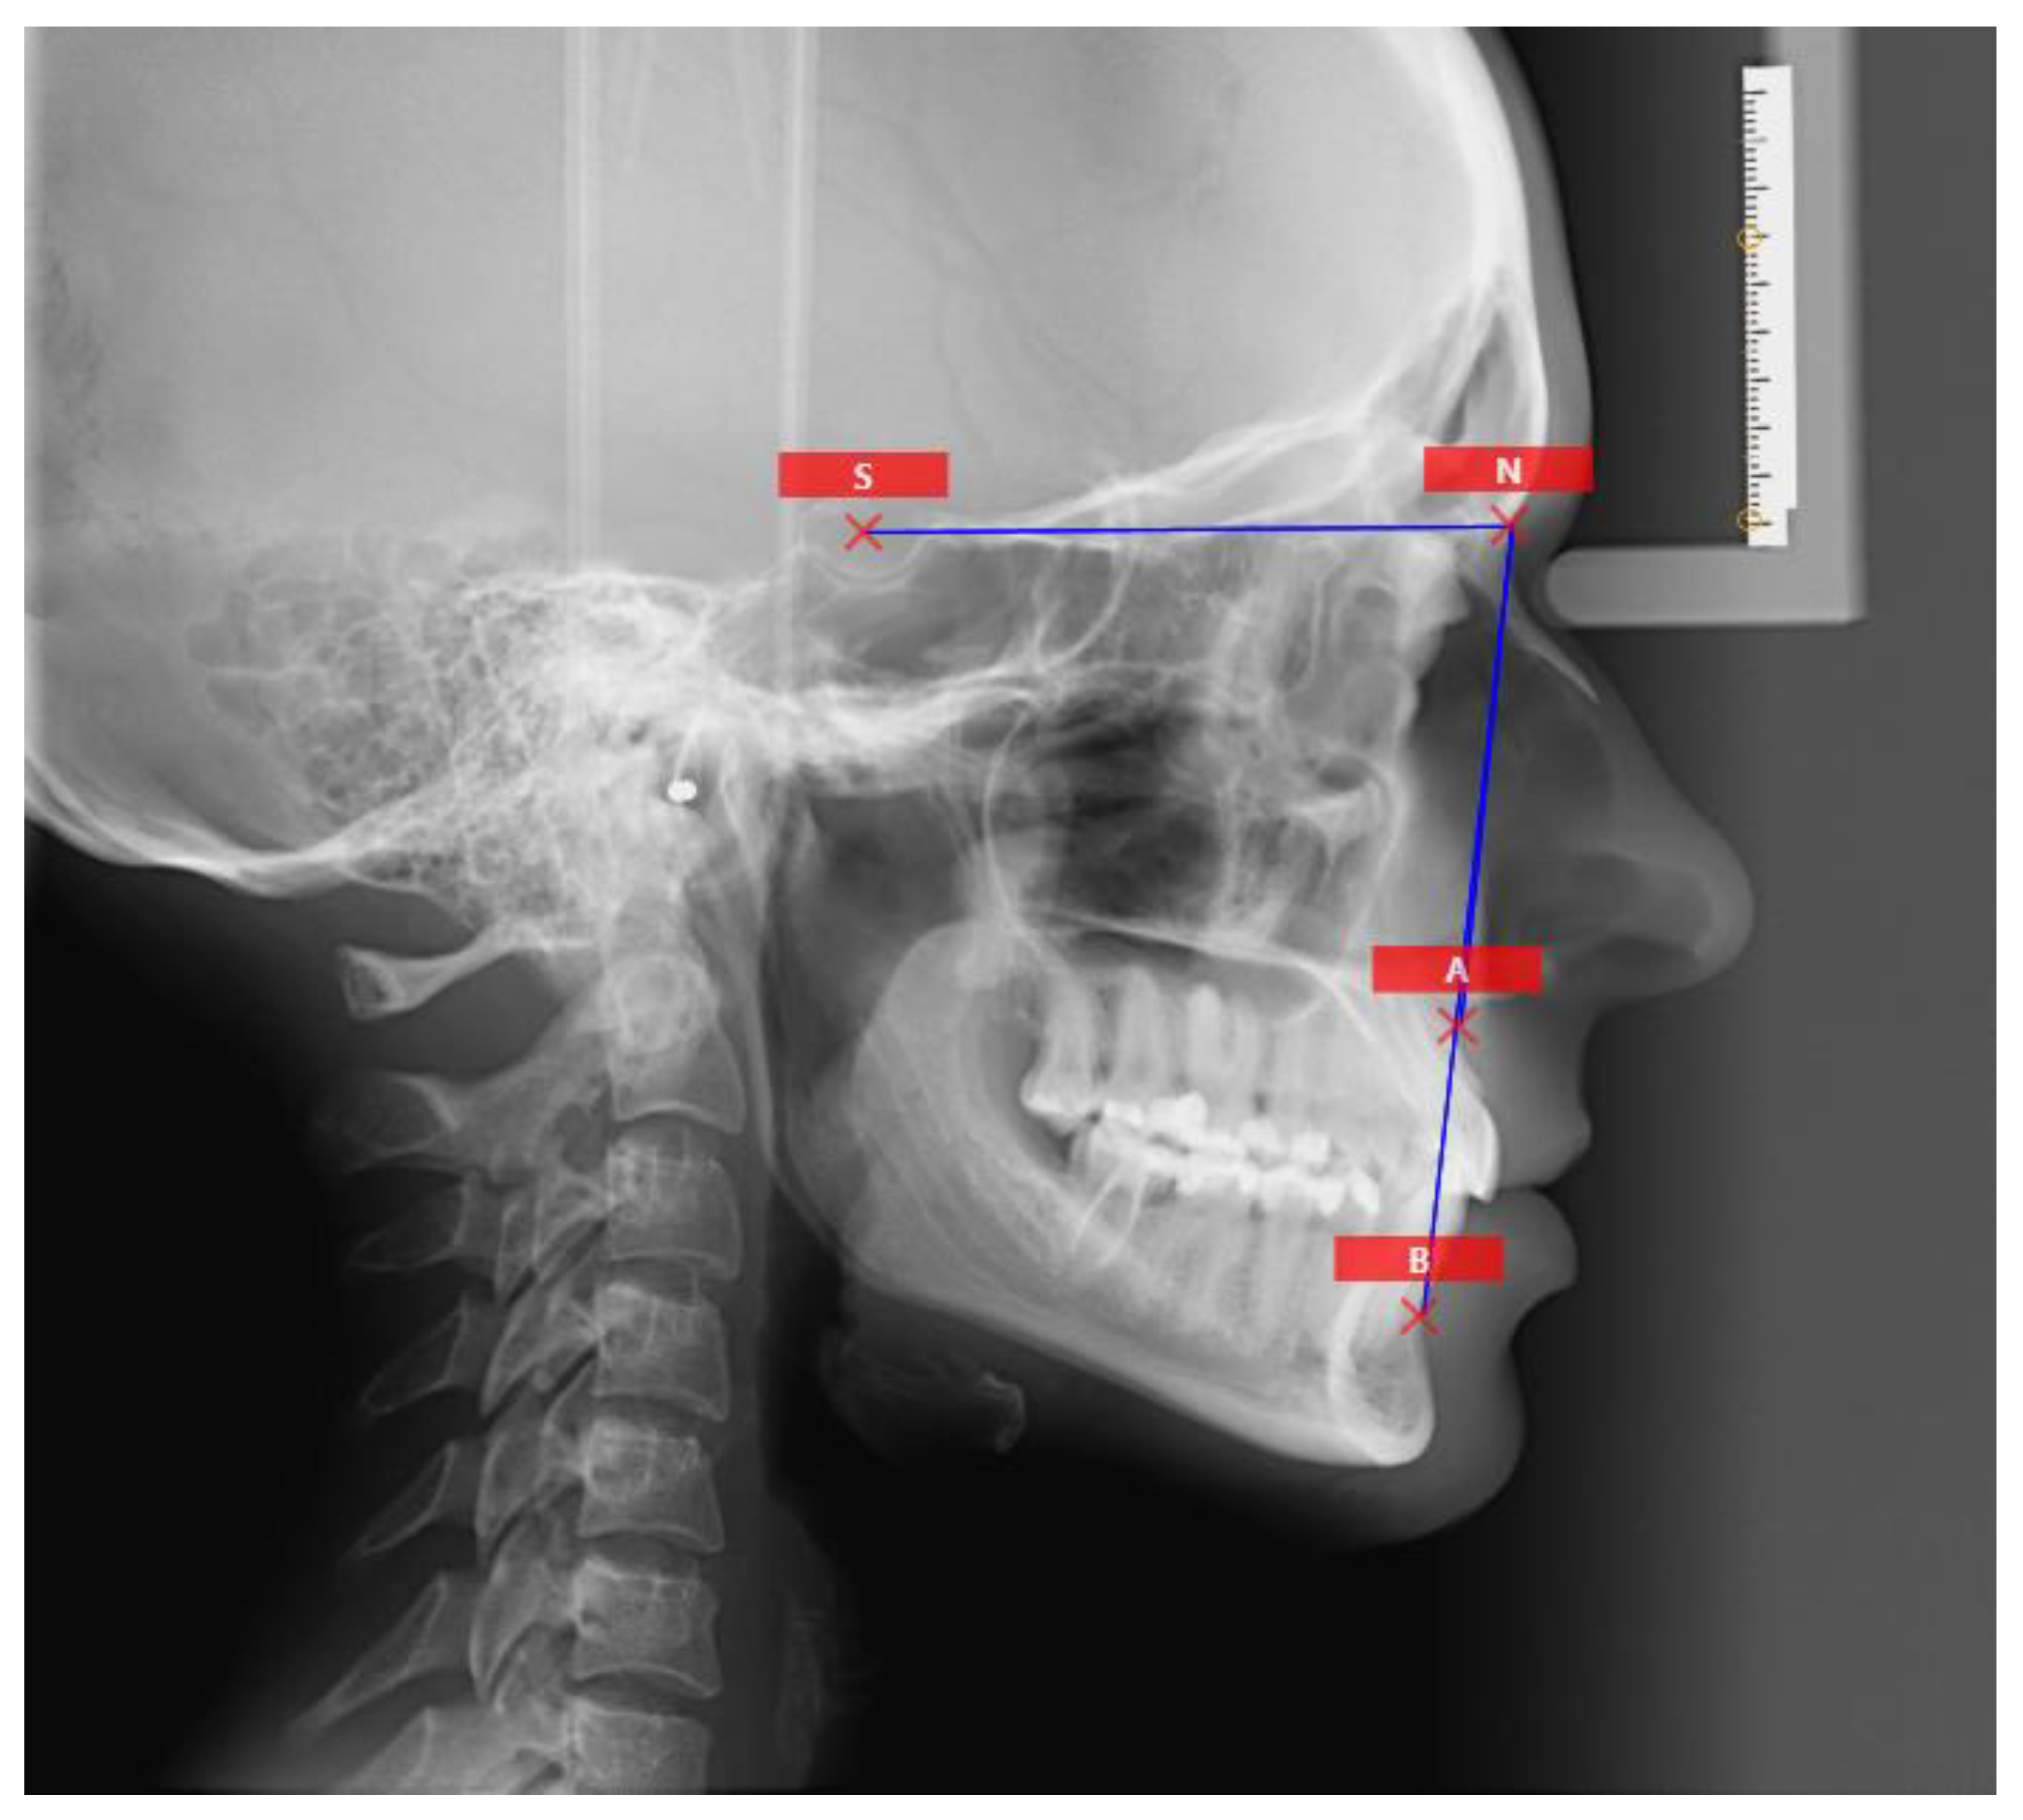

3.1. ANB Angle